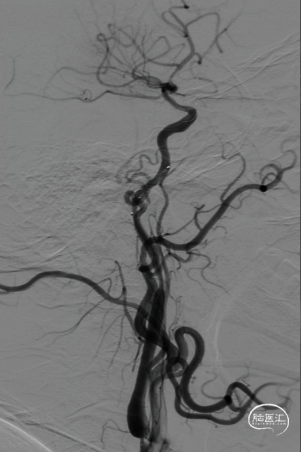

术前造影提示左侧颈内动脉自起始部闭塞,前交通动脉开放,同侧大脑前动脉及大脑后动脉皮层对左侧半球形成皮层侧支代偿。

微导管微导丝配合下多次尝试通过颈内动脉起始部闭塞段未能成功,在125mm多功能导管配合下,将微导管及Command微导丝成功越过颈内动脉起始部闭塞段,微导管造影确认在颈内动脉真腔,但远端未见显影,考虑血栓所致。静脉推注替罗非班8ml,并以6ml/h持续泵入。

交换出微导管及多功能导管,C2段放置SPIDER保护伞后以3-30mm球囊和6F 115cm SKATHI远端通路导管采用球囊接力技术越过颈内动脉闭塞段,由下及上持续抽吸。